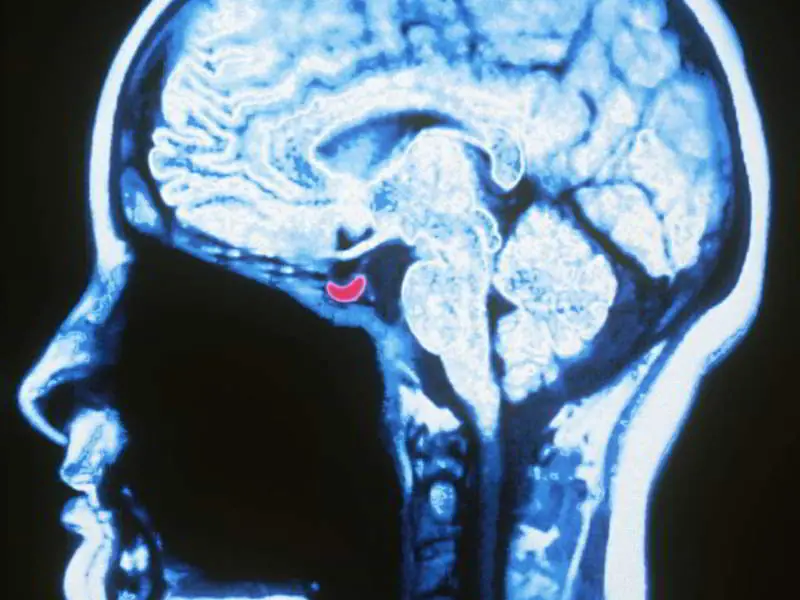

Esto es lo que pasa a tu cuerpo cuando te emborrachasEl hipotálamo  y la glándula pituitaria  (la parte roja de la imagen) también se deprimen por el alcohol y bajan su ritmo.

Normalmente, ellos controlan la liberación de hormonas y, sin su constante vigilancia, tus hormonas son libres de abalanzarse sobre cualquier cosa que pase por su camino. Entre el estallido de la hormona y la dopamina liberada por la presencia del alcohol, los centros de placer están bastante felices